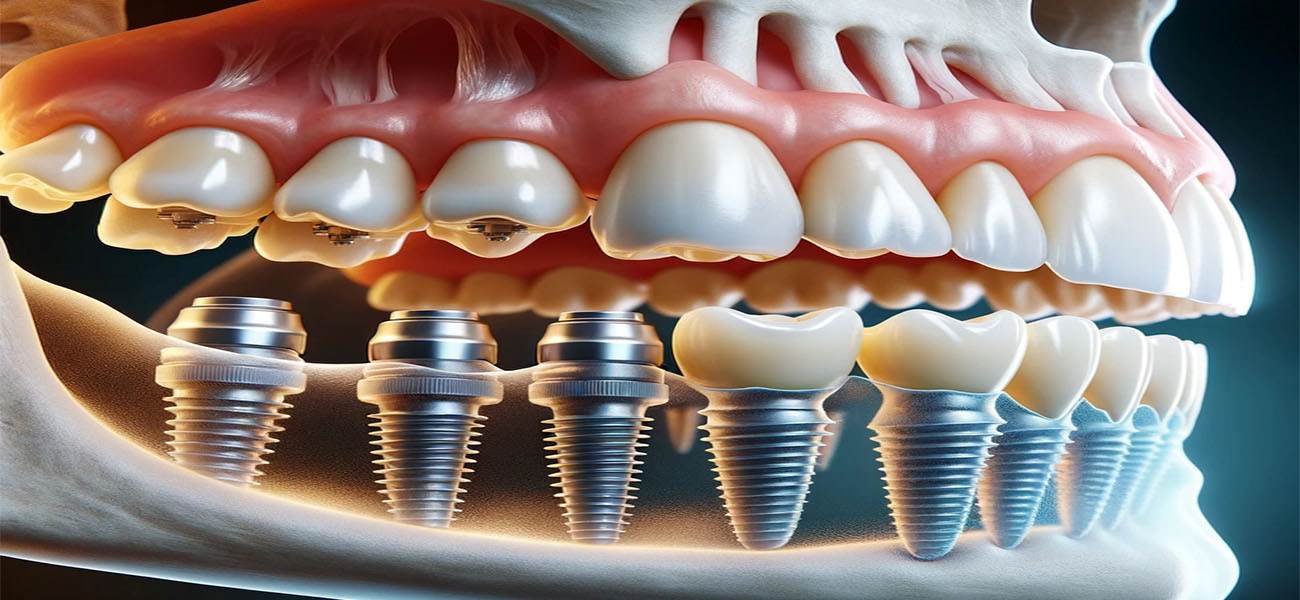

ایمپلنت دندان یکی از پیشرفتهترین و موثرترین روشها برای جایگزینی دندانهای از دست رفته است. این روش نه تنها به بهبود ظاهر لبخند کمک میکند، بلکه عملکرد جویدن و صحبت کردن را نیز بهبود میبخشد. در این مقاله به بررسی بهترین کلینیک ایمپلنت دندان در سعادت آباد، به ویژه کلینیک دکتر اللهیار گیاهپور، دندانپزشک و جراح دهان، فک و صورت خواهیم پرداخت. همچنین به مزایا و ویژگیهای این کلینیک، خدمات ارائه شده، و نظرات بیماران خواهیم پرداخت.( کلینیک دندانپزشکی دکتر گیاهپور, بهترین کلینیک ایمپلنت دندان در سعادت آباد کجاست؟ )

2. جراحی ایمپلنت

در این مرحله، ایمپلنت (پیچ تیتانیومی) در استخوان فک قرار داده میشود. این عمل معمولاً تحت بیحسی موضعی انجام میشود.

ایمپلنت دندان یک پیچ تیتانیومی است که به عنوان ریشه دندان مصنوعی در استخوان فک قرار میگیرد. پس از جوش خوردن ایمپلنت به استخوان، یک پروتز (دندان مصنوعی) روی آن قرار میگیرد. این روش به بازگرداندن عملکرد و زیبایی دندانهای از دست رفته کمک میکند.